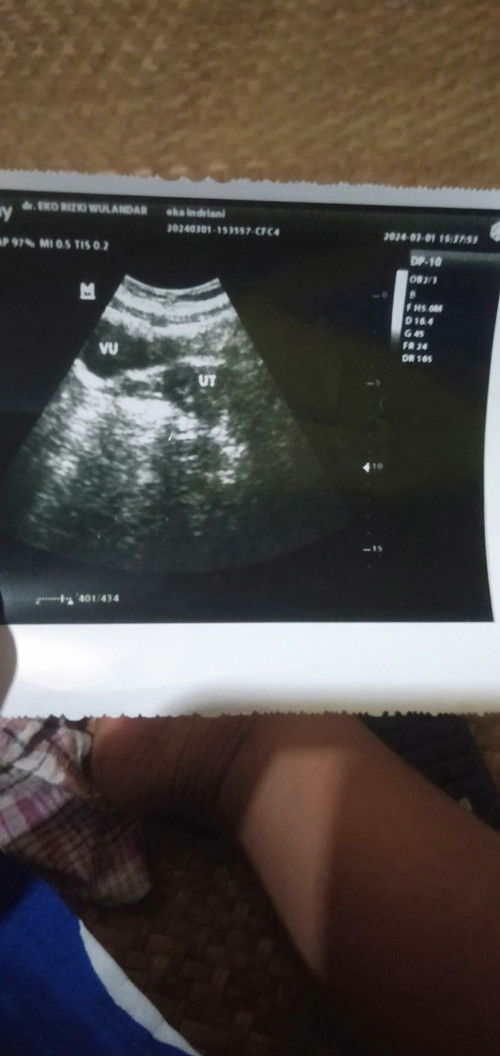

ga bun. usia kehamilan berapapun aman/normalnya gaada flek/darah, kecuali mendekati HPL sbg tanda mau lahiran. periksa ya bun ke dokter kandungan.

Ibu hamil